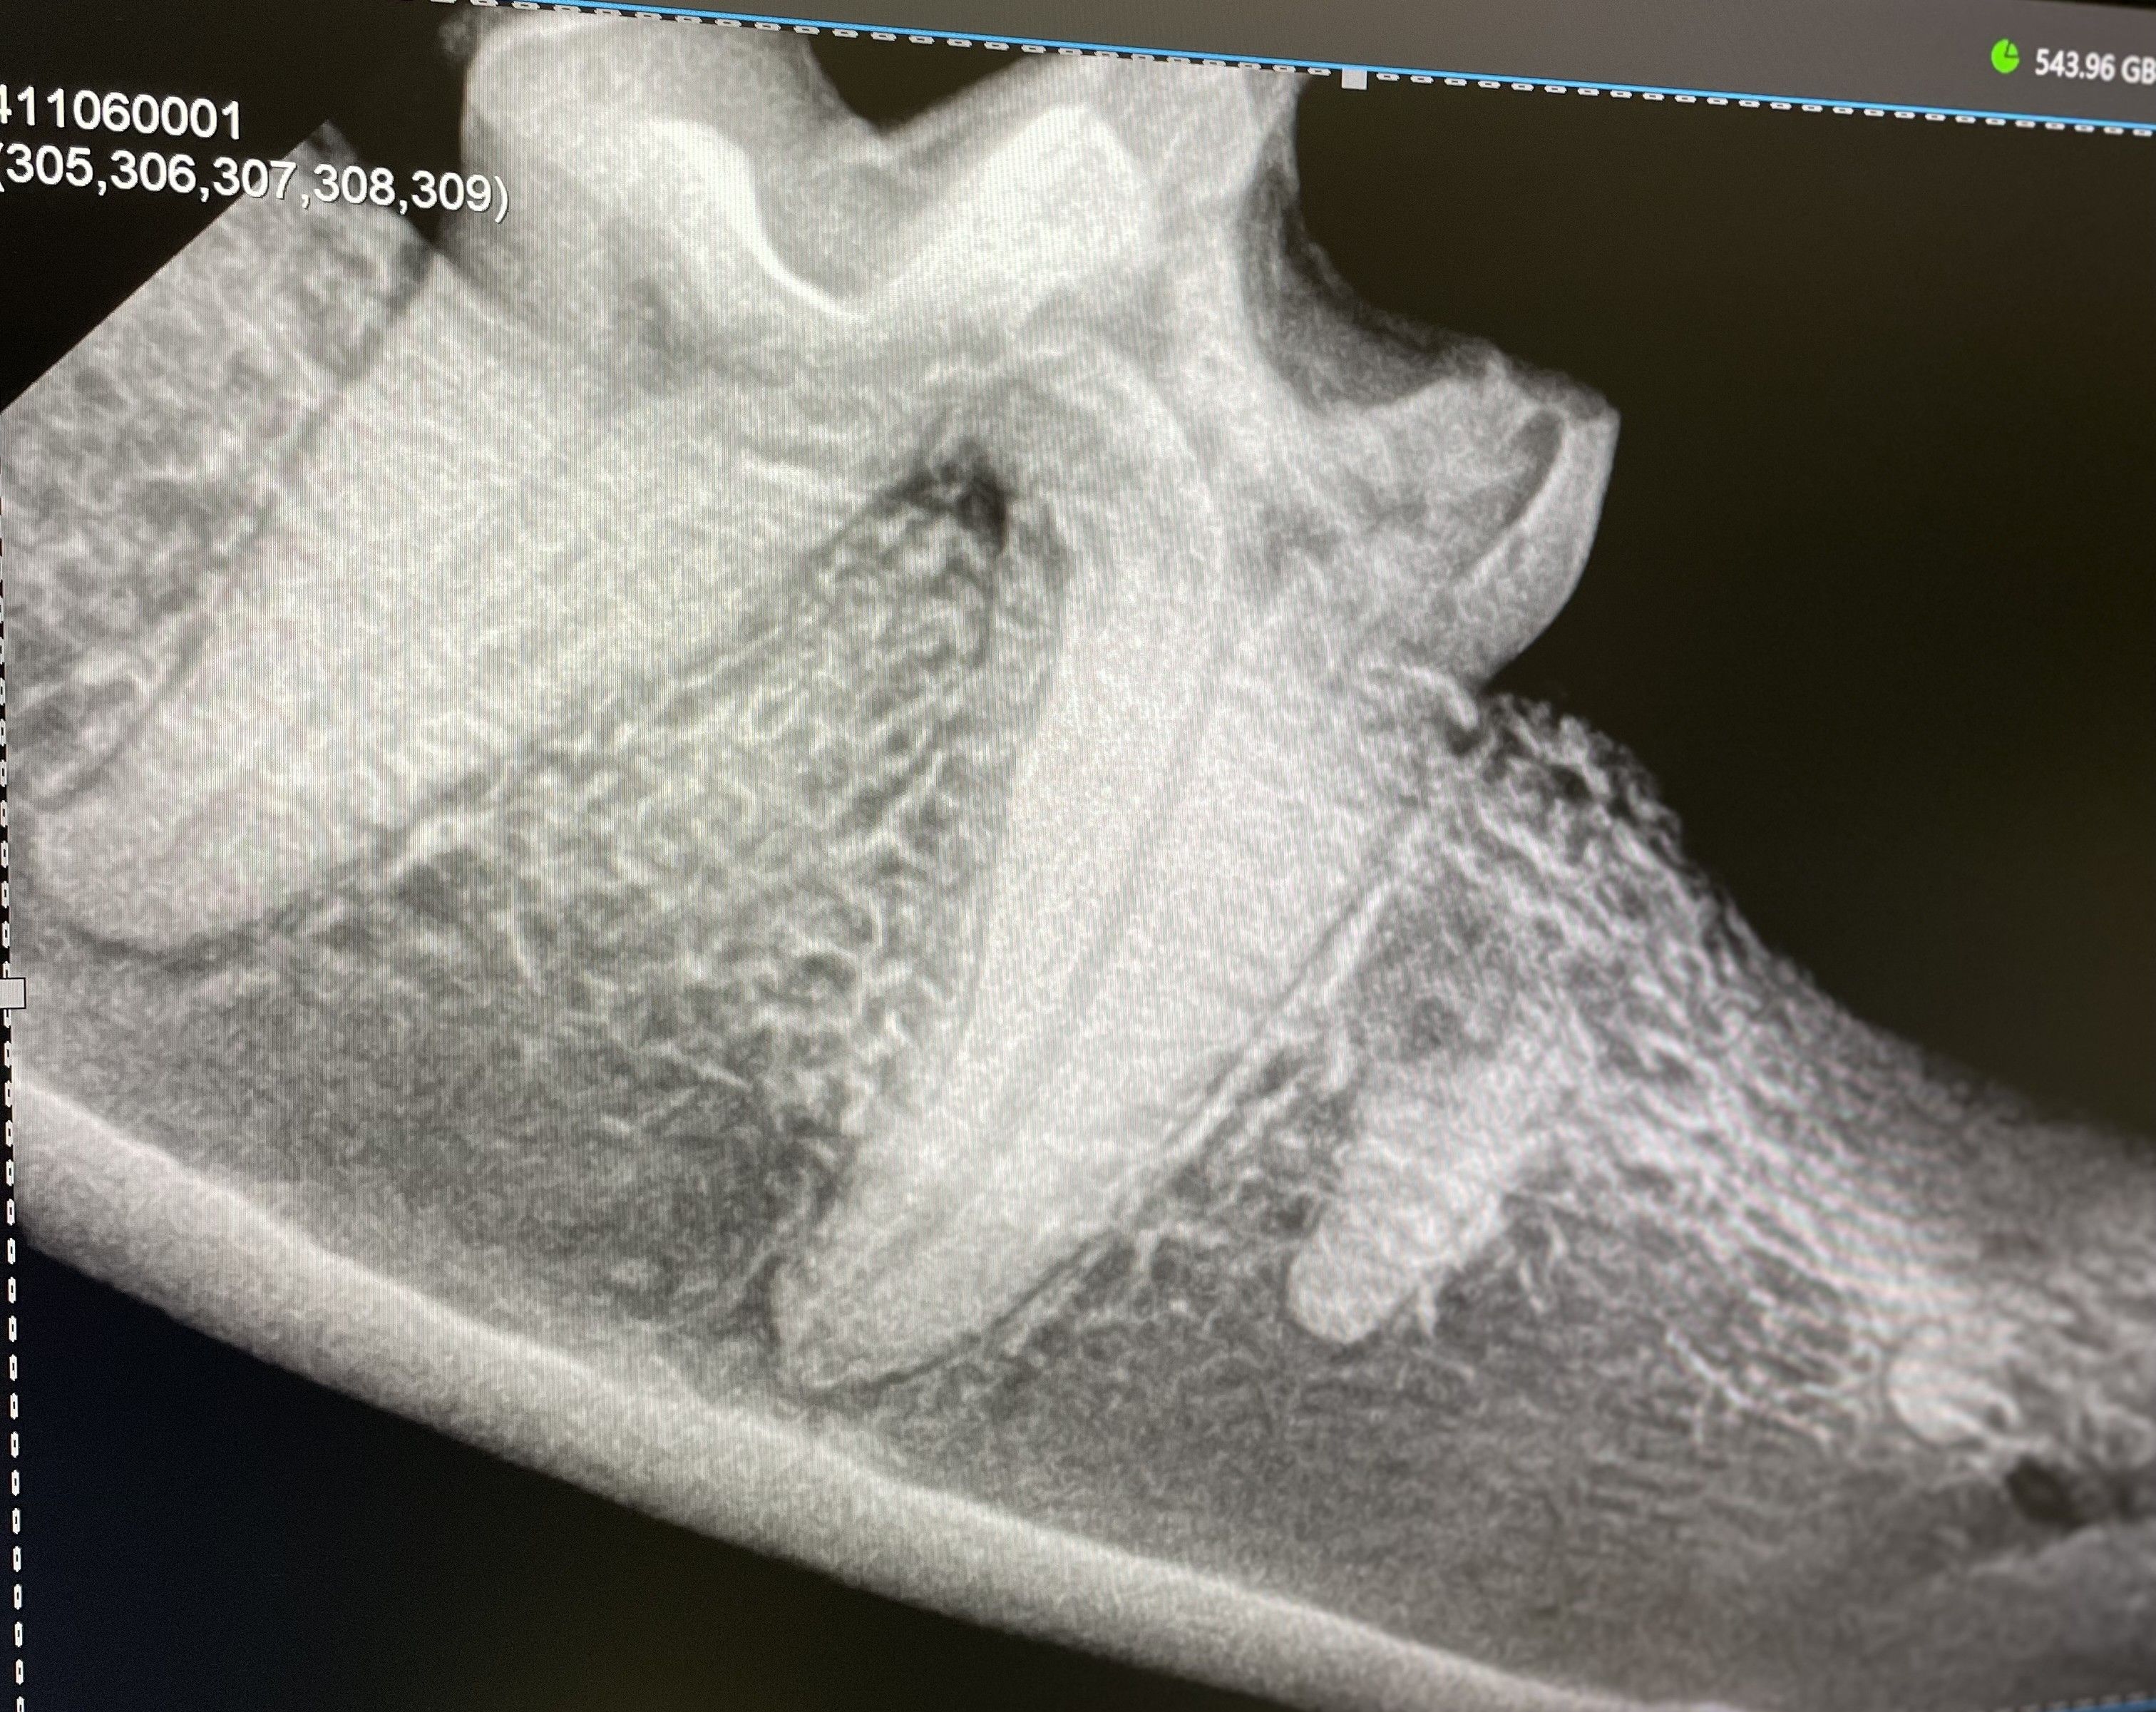

Ohne Zahnröntgen kann nur der sichtbare Teil des Zahnes und der Maulhöhle beurteilt werden. Sie sind unumgänglich, um „versteckte“ Probleme zu entdecken, wie z.B. Frakturen oder Abszesse der Zahnwurzeln, resorptive Läsionen (FORL) der Zähne bei der Katze, Entzündungen der Pulpahöhle (das ist das Innere des Zahnes) oder Veränderungen des Kieferknochens. Mit Hilfe des Zahnröntgens können auch von Geburt an bestehende Probleme wie Zahnzysten, Zahnfehlstellungen oder fehlende Zahnanlagen entdeckt werden.

Falls eine Zahnsanierung oder Behandlungen nicht auf einmal, sondern in zwei oder mehr Stadien durchgeführt werden, helfen Zahnröntgen auch bei der genauen Planung der weiteren Schritte. Außerdem kann damit ein Fortschreiten von Erkrankungen der Zähne oder des Kiefers überwacht werden. Und ganz wichtig: nach einer Zahnextraktion kann mit dem Zahnröntgen überprüft werden, ob auch alle Wurzelreste entfernt wurden.

Die Bilder werden intraoral erstellt, das heißt eine dünne und flexible Speicherfolie für die digitalen Bilder befindet sich für die Aufnahmen in der Maulhöhle des Tieres. Auf diese Weise ist die Qualität der Bilder am hochwertigsten. Um alle Zähne der Maulhöhle darzustellen sind im Normalfall zwischen 6 und 10 Aufnahmen nötig, die Bilder selber werden dann digital auf einem Bildschirm dargestellt. Die Strahlenbelastung ist beim intraoralen digitalen Röntgen übrigens extrem gering und stellt daher keine nennenswerte Gesundheitsbelastung für unsere Patienten dar.